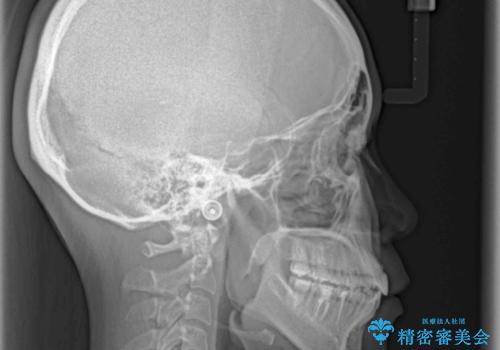

- 上下の前歯の反対咬合を気にして来院された患者様です。

インビザラインを用い、下顎はIPR(歯と歯の間を削る)と歯列全体を後方に移動させ、上顎は前歯を持ち上げることで、反対咬合を改善していくこととしました。